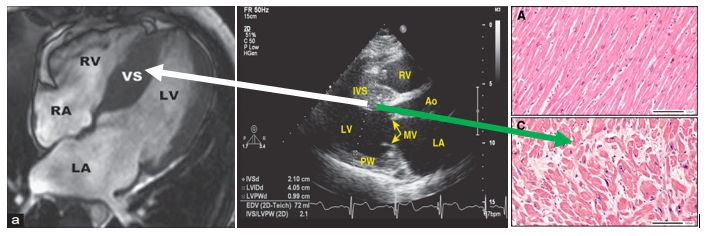

Υπερτροφική μυοκαρδιοπάθεια  HCM

Πολύπλοκη γονιδιακή νόσος με ανεξήγητη πρωτοπαθή πάχυνση σε τμήμα του μυϊκού

τοιχώματος της αριστερής κοιλίας, συνήθως στο μεσοκοιλιακό διάφραγμα, τουλάχιστον 15 mm. Είναι αρκετά συχνή: 1 / 400 ανθρώπους στο γενικό πληθυσμό. Οφείλεται σε γνωστή μετάλλαξη γονιδίου (στο 50 – 60%)  που δημιουργεί μείωση της λειτουργικότητας των πρωτεϊνών των μυοκυττάρων και κυρίως της μυοσίνης (60% )  ακτίνης, τροπομυοσίνης, τιτίνης, τροπονίνης

Η ΔΙΑΓΝΩΣΗ ΤΗΣ HCM

Η διάγνωση της HCM γίνεται όταν υπάρχει ανεξήγητη πάχυνση σε περιοχή του τοιχώματος της Αριστερής Κοιλίας – τουλάχιστον 15 mmτουλάχιστον 13 mm αν αυτή βρεθεί είτε σε συγγενή ανθρώπου με γνωστή HCM είτε σε άνθρωπο που έχει μεταλλαγμένο γονίδιο της πρωτεΐνης του σαρκομεριδίου). Για την διάγνωση χρησιμεύουν:   Yπερηχοκαρδιογράφημα, Καρδιακή Μαγνητική Τομογραφία (CMR), ΗΚΓ (μη ειδικές αλλοιώσεις, υπερτροφία της αριστερής κοιλίας με διαταραχές επαναπολώσεως και ίσως Q στις κατώτερες ή πλάγιες απαγωγές), Holter (για πιθανή ανεύρεση κοιλιακής ταχυκαρδίας).